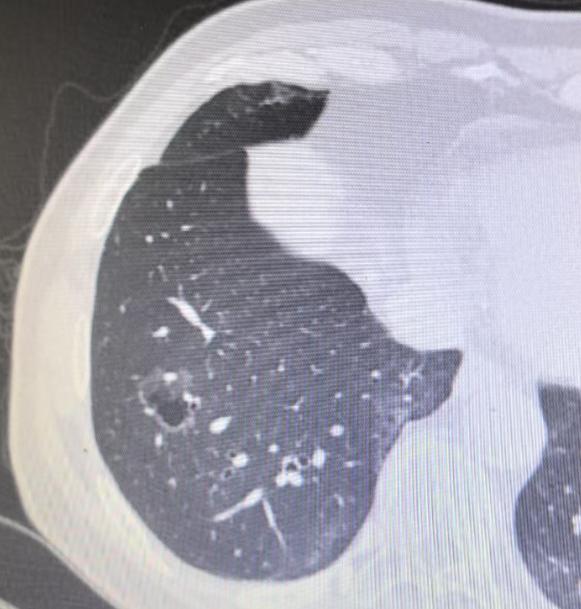

我的同行,一位 75 岁的医务工作者,6年前体检偶然查出的肺病灶,之后便一直处于观察状态。期间,大家普遍认为这只是肺大泡或肺气肿,并未过多警惕。 直到大概 4 年前,情况有了转折!当时他的太太因肺结节被确诊为早期肺癌,我为他太太主刀手术时,顺便仔细查看了他的肺部影像,当即提出一个不同的判断:这很可能是囊腔型肺癌,而非此前认为的良性病变。 今年,他再次复查,结果显示病灶较 2019 年明显增大 ——2019 年时病灶仅 1 公分,如今已长到两点几公分。 结合影像特征和病情进展,我判断早期肺癌的可能性极大,因此近期为他安排了手术。 其实,囊腔型肺癌近年来并不少见,仅这两个礼拜,我就接诊了十几例这类患者。很多人都会有疑问:为什么肺癌会呈现囊腔形态?囊腔型肺癌到底严重吗? 这里要跟大家说清楚:囊腔型肺癌的严重程度,关键看病灶内的软组织成分。如果软组织成分少,它的性质就类似原位癌或微浸润癌,恶性程度较低,预后也较好。 就像这位 75 岁的患者,虽然病灶体积增大了,但内部软组织成分很少,术后病理结果也证实是微浸润癌。 这类肺癌之所以会形成囊腔,核心原因是肿瘤细胞仅沿着肺泡壁生长,并不向外侵犯。在生长过程中,肿瘤细胞会产生一定张力,导致肺泡逐渐扩张,最终形成我们看到的囊腔形态。 之前还有病友特意打电话问我,说有人写文章说囊腔型肺癌很严重,为此十分担心。但事实上,大多数薄壁、软组织成分少的囊腔型肺癌,都属于早期病变,只要及时通过手术处理,术后通常不需要进行放化疗等后续治疗,治愈率很高。 当然,即便属于早期,一旦发现病灶有增大趋势,还是要尽早手术干预,避免病情进一步发展。[玫瑰][作揖]